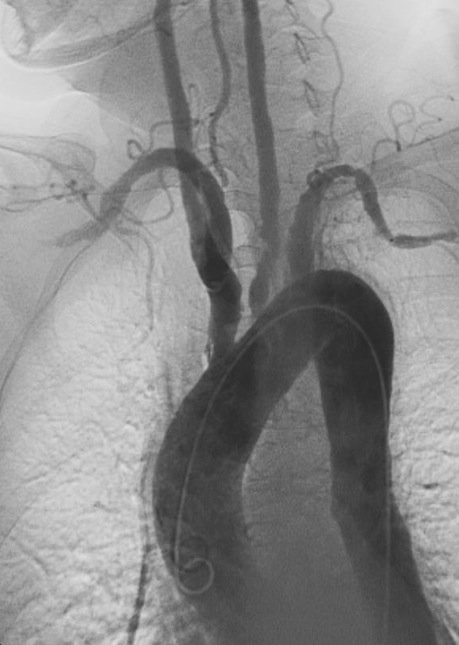

Case of the week 🧩

Patient not a surgical candidate.

Received a carotid stent — sharing pre-, post-stent, and IVUS images below.

👉 How do you interpret the findings?

👉 What would your next step be in management?

#CardioTwitter #Endovascular